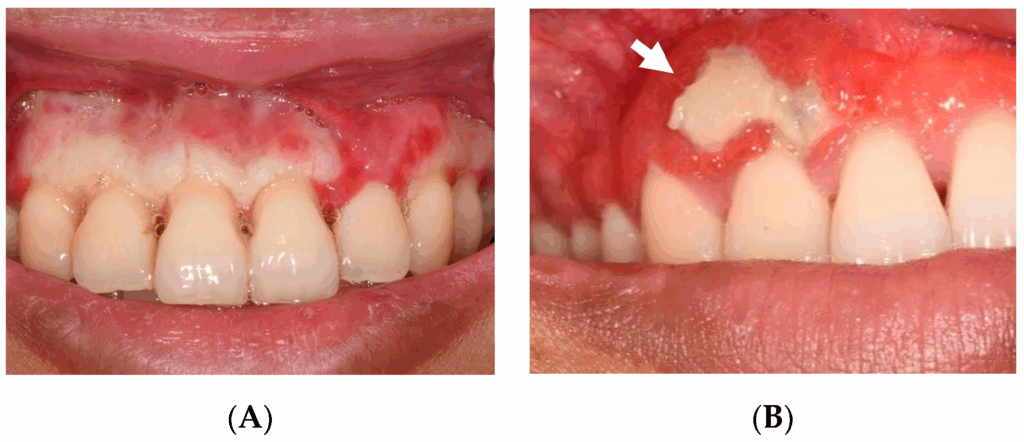

في الستينات، ظهرت تقارير إن نوفالجين ممكن يسبب حالة اسمها Agranulocytoses ، ودي حالة نادرة بتقلل كرات الدم البيضا بشدة، فبتزود مخاطر الإصابة بالعدوى. الحالة دي بتحصل غالبًا بسبب تفاعل مناعي أو سمية مباشرة على نخاع العظم بشكل بشبه الΝeutropenia اللي كنا اتكلمنا عليها مع Neupogen .

الموضوع تم ملاحظته في الدول الإسكندنافية في البداية . مريض بياخد نوفالجين و بعد فترة تبدأ مرة واحدة حرارة عالية – تعب ووضعف عام شديد – التهاب في الحلق و اللثة و الأغشية المخاطية – عدوى في الجهاز التنفسي و تدهور سريع جدا في الحالة . و تم تسجيل اكثر من حالة وفاة . و العكس المرضى اللي بتظهر عليهم الاعراض و بيقرروا يوقفوا النوفالجين بتكون امكانية انقاذهم اعلى .